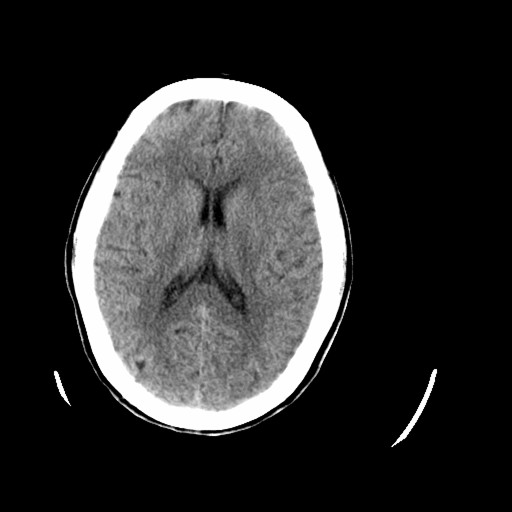

标题: CT16233:女,44岁,智障多年,现感头痛 [打印本页]

标题: CT16233:女,44岁,智障多年,现感头痛

老年脑,萎缩表现

脑萎缩

44岁  小脑表现为萎缩? 原因是什么呢?ct诊断上可报小脑萎缩吗?

橄榄桥小脑萎缩.左侧小脑脚腔梗.

为什么不考虑发育畸形呢

1)小脑萎缩。2)小脑蚓部发育不良。